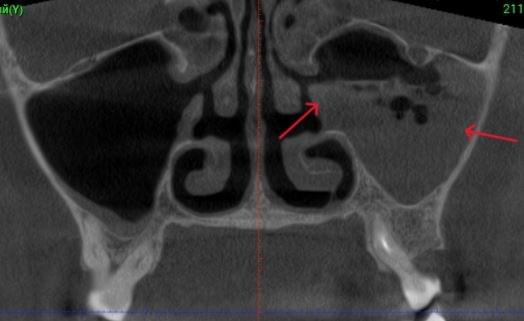

Діагностика гайморових пазух за допомогою КТ

У сучасній медицині КТ придаткових пазух носа (або КТ синусів) — це «золотий стандарт»

діагностики для ЛОР-лікарів та щелепно-лицевих хірургів. Звичайний рентген часто не

показує повну картину, а МРТ не завжди доступний і дорожчий. Комп’ютерна томографія дає

детальну 3D-модель усіх пазух (гайморових, лобних, клиновидних та решітчастого

лабіринту) за 10 секунд і з мінімальною дозою опромінення.

КПКТ (конусно-променева комп’ютерна томографія) — це 3D-знімок високої роздільної здатності. На відміну від звичайного рентгену, КТ показує: